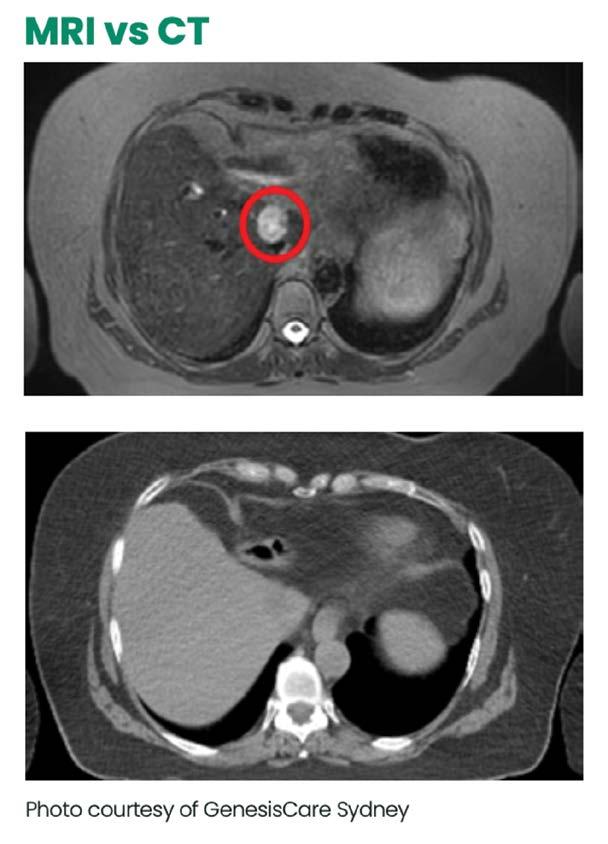

HΟγκολογίας, Ιατρική

ΕΚΠΑ, Α’ Εργαστήριο

Αρεταίειο Πανεπιστημιακό

Νοσοκομείο, παρουσίασε το Cyberknife

για στερεοτακτική ακτινοχειρουργική ή α-

υψηλές δόσεις ακτινοθεραπείας σε συγκε-

σημείο, στο οποίο βρίσκεται ο όγκος, ενώ ταυτόχρονα ελαχιστοποιούνται